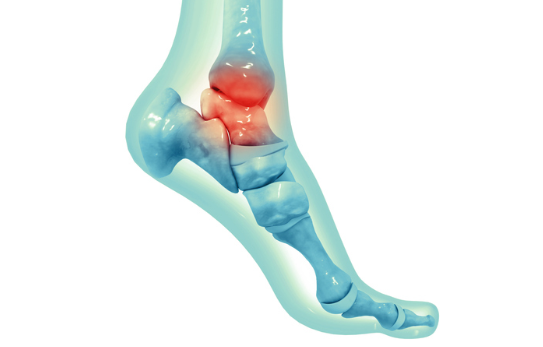

발목 통증?

발목 통증은 발목관절에 느껴지는 불편감이나 통증을 말합니다. 경증부터 중증까지 다양하며 갑자기 발생하거나 시간이 지남에 따라 점진적으로 발생할 수 있습니다. 발목 통증은 한쪽 또는 양쪽 발목에 영향을 미칠 수 있으며 다양한 요인에 의해 발생할 수 있습니다.